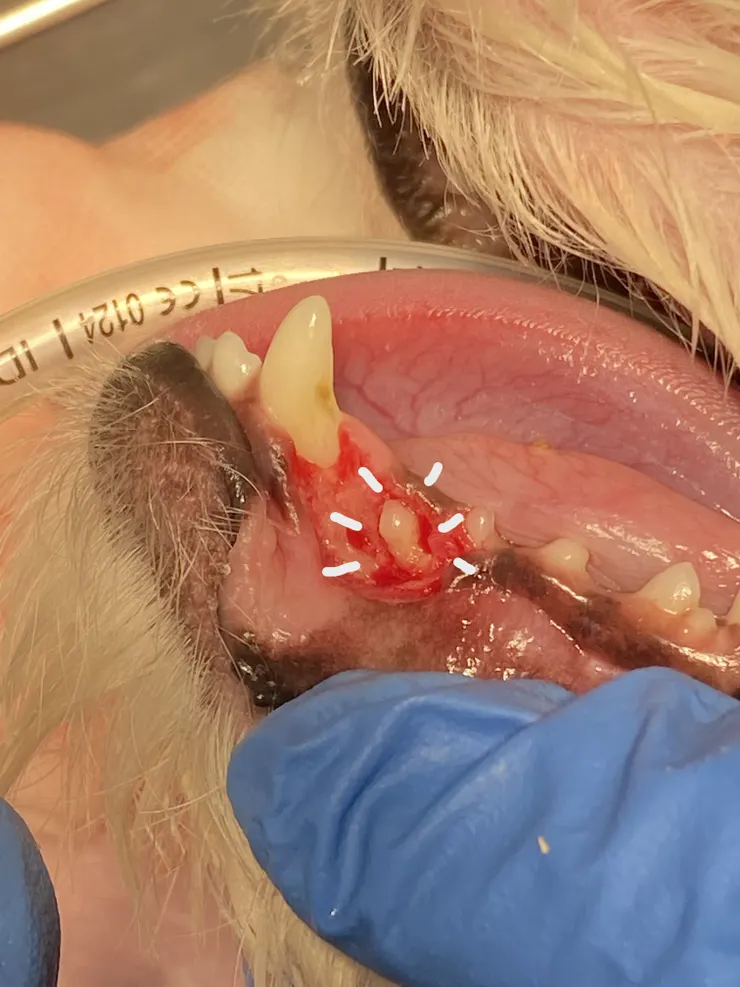

乳牙必須拔除,必須正視它的影響對,不能。或許看起來很可愛,但實際上殘留的乳牙不僅會造成牙周問題,關係到咬合狀況,有時候也會影響到正常恆牙的發育,簡單來說就是佔據別人的空間,讓恆牙長不出來被包覆在骨頭裡面,形成另一個更麻煩的問題:含牙囊腫 (Dentigerous cyst),這是一件很不舒服的事情,更需要依賴齒科X光與經驗豐富的操作,才能順利將包埋在骨頭裡面的恆牙拔除

無法順利掉下來的乳牙建議必須拔掉,然而拔乳牙也並非想像的這麼容易,一般我們將拔乳牙視為手術性的拔牙,意思就是必須切開牙齦,打磨掉部分骨頭才能順利拔乾淨,因為乳牙的牙根通常都十分的細長,一個不小心是有機會拔斷的喔,因此建議拔乳牙時尋找具備齒科x光的醫院進行確認,避免沒有拔乾淨的問題。